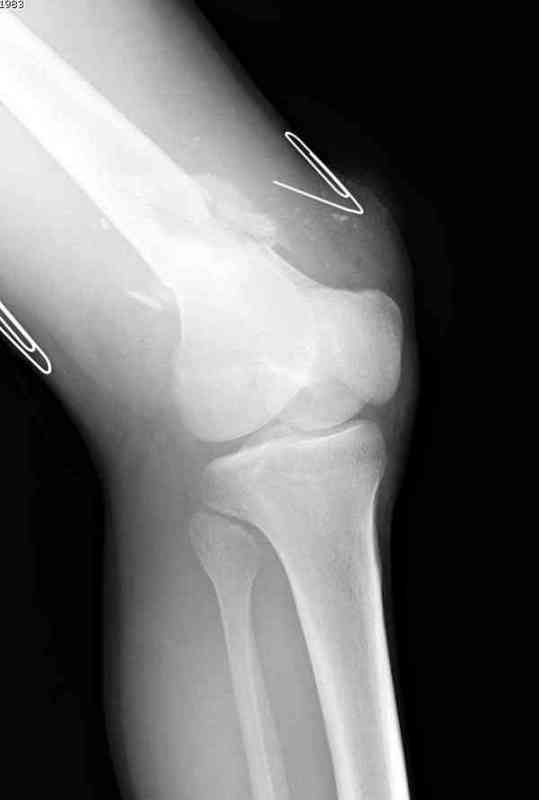

Укороченный фрагмент с самого начала являлся проблемным, на рентгене не видны следы от множественных спиц, обычно применяемых для лечения "коротких" переломов.

Адекватную фиксацию можно получить путем экстрафокальной косой остеотомии более проксимально, тем самым удлинить дистальный фрагмент, без повторной работы в фокусе патологии, что, в свою очередь, приведет к еще большему укорочению фрагмента.

Как предлагают коллеги, свежие стрессовые снимки уточнят наличие подвижности, а длинный на всю длину конечности снимок позволит провести точный предоперационный расчет по коррекции.

Предпочтительно фиксацию провести пластинами, во-первых, можно было сделать квадрицепс-пластику по Judet для восстановления движения в суставе, а потом коррекцию и фиксацию кондилярной пластиной с угловой стабильностью. Стерильный турникет на конечность поможет уменьшить кровепотерю во время операции.

До выхода Locking Plate, 95 градусная Blade Plate считалась одним из первых locking concept и фаворитов в лечении супракондилярных переломов и осложнений, потому что лезвие внедряясь параллельно к суставу, что создавало хорошую фиксацию. Для усиления фиксации иногда применяли Schuhli nut, чтобы блокировать шуруп в отверстии